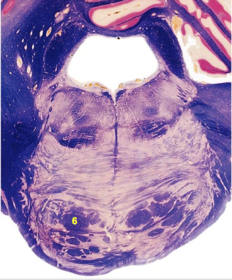

| Anterior spinocerebellar tract | |

| CN IX | |

| Inferior cerebellar peduncle | |

| Inferior olivary complex | |

| Dorsal cochlear nucleus | |

| Inferior vestibular nucleus | |

| Medial vestibular nucleus | |

| Spinal nucleus of V | |

| Spinal tract of V | |

| Medullary pyramids | |

| Solitary nucleus | |

| ALS | |

| Medial lemniscus | |

| Medial longitudinal fasciculus | |

| Ventral cochlear nucleus | |

| Central tegmental tract | |

| Olivary internal arcuate fibers | |

| Solitary tract | |